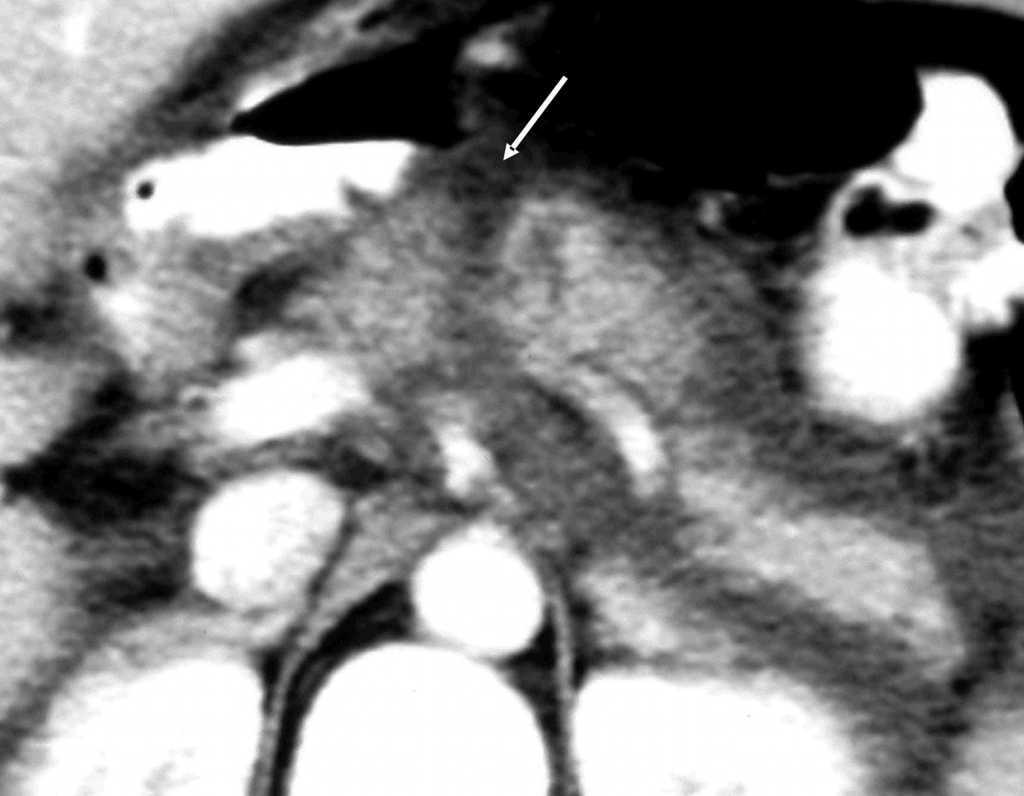

Paciente de 32 años de edad sin antecedentes de interés que presenta un accidente de coche por choque directo frontal. Es trasladado a urgencias de un hospital comarcal. En dicho centro permanece estable desde el punto de vista hemodinámico y respiratorio. No presenta traumatismo craneoencefálico. Escala de coma de Glasgow (GCS): 15. Erosiones faciales múltiples. Refiere dolor esternal y costal izquierdo a la palpación objetivándose imagen radiológica de fractura de la quinta costilla izquierda y del tercio inferior de esternón, así como contusión pulmonar bilateral de predominio izquierdo. Presenta dolor abdominal difuso a la palpación. No hay lesiones de partes blandas ni del aparato locomotor. En la analítica de ingreso únicamente destacar una creatinina ligeramente elevada (1,6 mg/dl) con intensa hematuria. Se realiza ecografía abdominal, visualizándose escaso líquido intraperitoneal en saco de Douglas, perihepático y periesplénico sin otras alteraciones, por lo cual se realiza tomografía computarizada (TC) abdominal donde se aprecia contusión hepática con líquido libre intraperitoneal en pequeña cantidad sin otras alteraciones. Ingresa en observación. Durante su estancia en planta permanece hemodinámicamente estable sin precisar fármacos vasoactivos ni transfusión de hemoderivados. De forma progresiva presenta distensión abdominal y dolor difuso en la exploración junto con elevación de amilasa sérica (546 UI), por lo que tres días después del accidente se repite TC abdominal donde se aprecia un hematoma subcapsular tipo II de 3 cm en el segmento 4B del lóbulo izquierdo del hígado con vesícula y vías biliares normales. En el páncreas (fig. 1) se observa un área hipodensa en cuerpo que afecta a todo el grosor pancreático sugestivo de solución de continuidad, ocasionado por sección traumática probablemente completa. Abundante colección peripancreática que se extiende a fascia de Gerota. Moderada cantidad de líquido libre intraperitoneal perihepático y periesplénico. Bazo y riñones normales. El paciente es trasladado a nuestro centro (hospital de referencia) para control y tratamiento. A su ingreso en nuestra Unidad de Medicina Intensiva el paciente mantiene la hemodinámica (presión arterial media [PAM] = 80 mmHg) a expensas de una taquicardia sinusal a 130 lpm, sin otros datos relevantes. Se decide intervención quirúrgica urgente donde se encuentra un hemoperitoneo de aproximadamente 600 cc. El páncreas presenta dos importantes laceraciones a nivel de cabeza-cuello y cuerpo con sección prácticamente total, y existe una importante peritonitis química generalizada. Se revisan estructuras vasculares, hígado, bazo y asas intestinales, incluyendo duodeno, sin encontrar lesiones. Se realiza pancreatectomía corporocaudal y esplenectomía. Posteriormente reingresa en la Unidad de Cuidados Intensivos (UCI). El postoperatorio fue tórpido dado que presentó un síndrome de disfunción multiorgánica consistente en fallo pulmonar (síndrome de distrés respiratorio agudo) y hemodinámico, junto con disfunción hepática, intestinal y hematológica. Precisó conexión a ventilación mecánica durante 17 días y fue necesaria la realización de traqueostomía percutánea. Se colocó sonda nasoyeyunal para alimentación enteral. Presentó una fístula pancreática de bajo débito que evolucionó favorablemente con medidas conservadoras. Fue dado de alta de nuestra Unidad de Medicina Intensiva a los 20 días postintervención quirúrgica.

Figura 1. Imagen de TC abdominal al tercer día del accidente: obsérvese la flecha que indica la sección del páncreas.